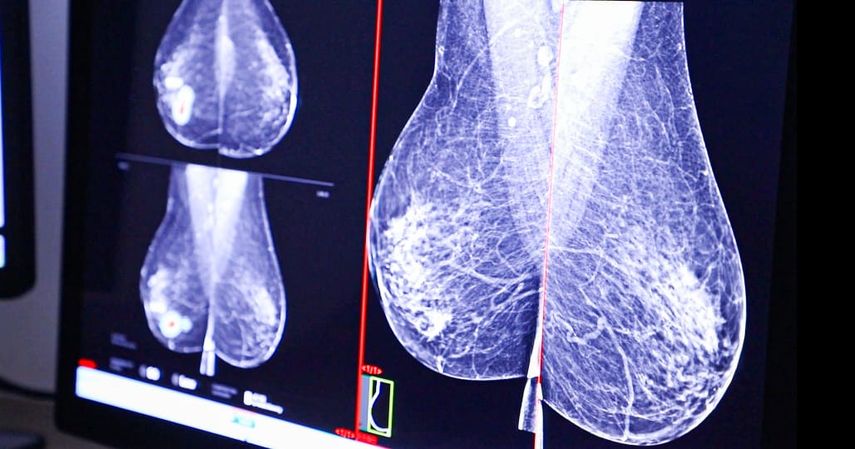

La Caja de Seguro Social (CSS) avanza en la modernización de sus servicios oncológicos con la incorporación de una nueva técnica de localización de lesiones mamarias que mejora la precisión y seguridad en las cirugías de cáncer de mama.

A diferencia del método anterior, el reflector puede colocarse días o incluso semanas antes de la cirugía, es mínimamente invasivo y mejora la experiencia de la paciente. El proceso se realiza bajo anestesia local utilizando una aguja especial, y durante la operación el reflector es localizado por medio de una sonda electromagnética, lo que permite resecciones más precisas y la conservación de mayor cantidad de tejido sano.